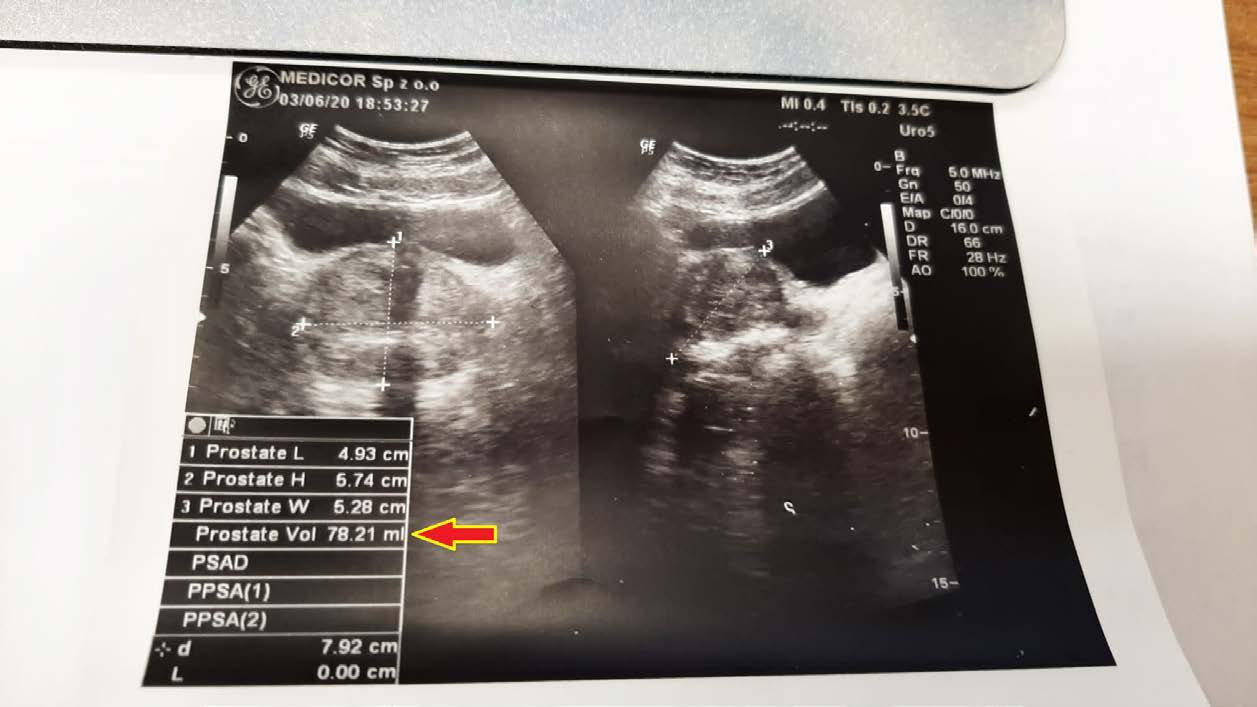

A 50-year-old man with an enlarged prostate, although mild hyperplasia, experienced pain and discomfort when urinating. His prostate volume at diagnosis was 78.21 ml (78.21 cm3). After unsuccessful attempts with finasteride, an attempt was made to reduce the size of the prostate with a drug. As seen in follow-up ultrasound images, the reduction was significant, reaching 55.97 ml (55.97 cm3) after just 2.5 months of therapy.